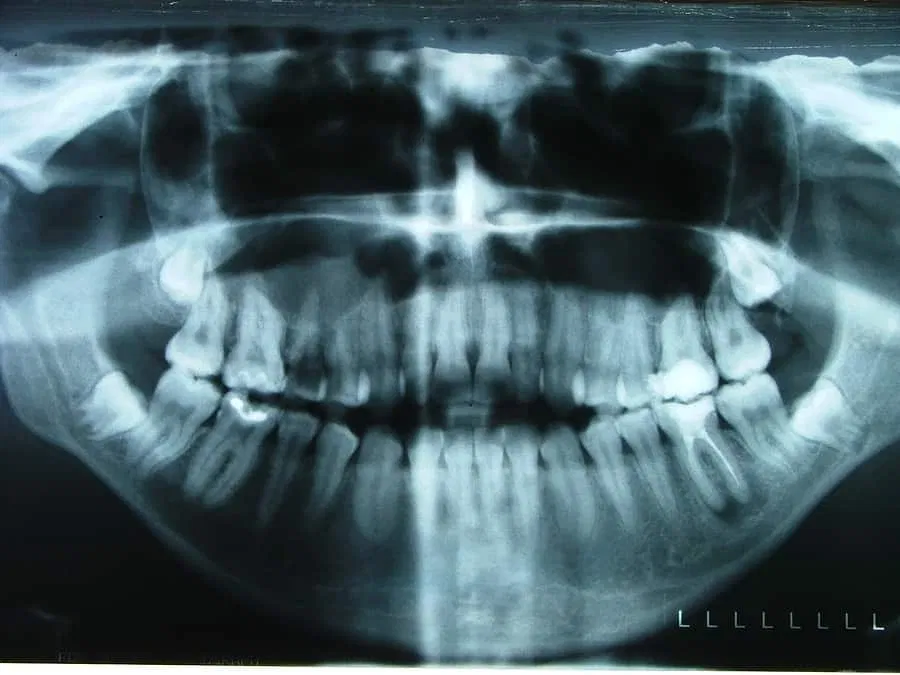

Written by Omaid K. Ahmad, BDS, MDentSc, FACP, and Andrew R. Chapokas, DMD, MSD, FACP, for the American College of Prosthodontists The advent of the dental implant revolutionized the field of dentistry. Implants are prostheses considered for replacement of teeth....